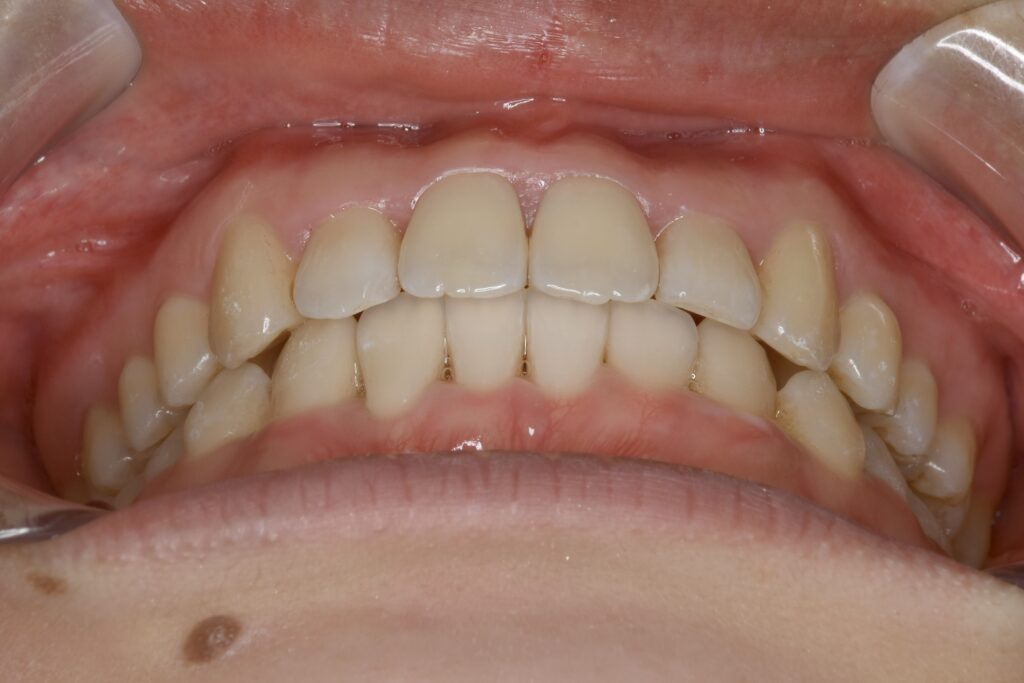

21歳 女性 治療期間:1年1ヶ月

叢生(ガタガタ)

マウスピース矯正装置(インビザライン)

非抜歯

BEFORE

AFTER

診断名・主な症状

叢生

治療内容

上下とも歯並びの横幅を広げながら、でこぼこを解消しました。

マウスピース矯正(インビザライン)

抜歯あり(智歯抜歯)

治療期間

1年1ヶ月

通院回数

10回

費用

85万円程度(税別)

リスク・副作用

痛み、歯肉退縮、歯根吸収、抜歯に伴う出血や腫れが生じることがあります。